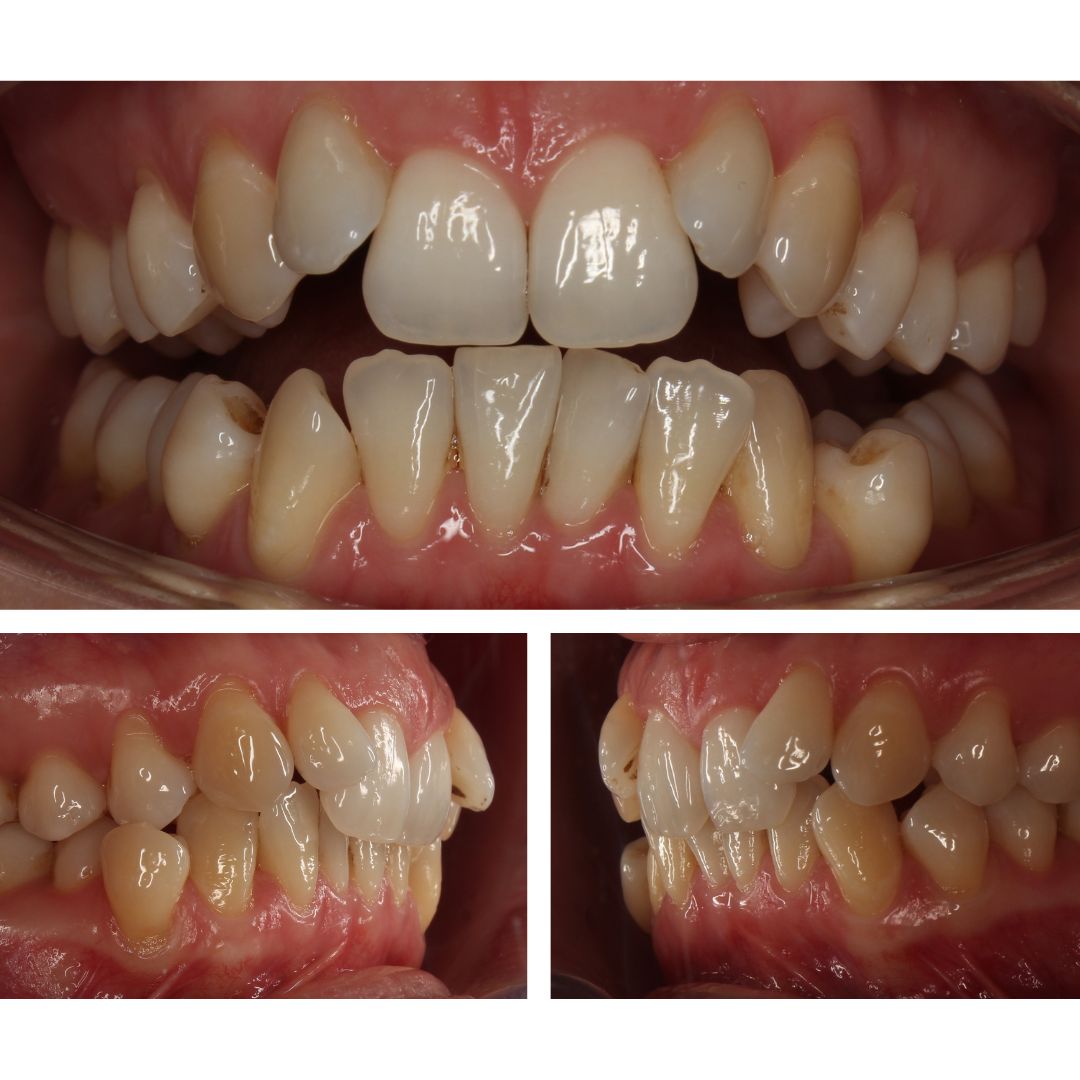

Пациентка обратилась в клинику «Норд Дентал» с запросом на улучшение эстетики улыбки.

Обследование показало:

- Сильную скученность зубов

- Дефицит места для постановки зубов в ровный ряд

- Наличии тонкого биотипа десны

☝️ Ортодонтическое лечение пациентов с тонким биотипом десны требует особенно внимательного подхода при расчете нагрузок, поскольку избыточная нагрузка при перемещении зубов может привести к рецессии десны (оголению корней).

👉 А ЕЩЕ НАМ НУЖНО БЫЛО РЕШИТЬ: как при сильной скученности зубов и дефиците места, поставить все зубы в ровный ряд и при этом обойтись без удаления зубов?